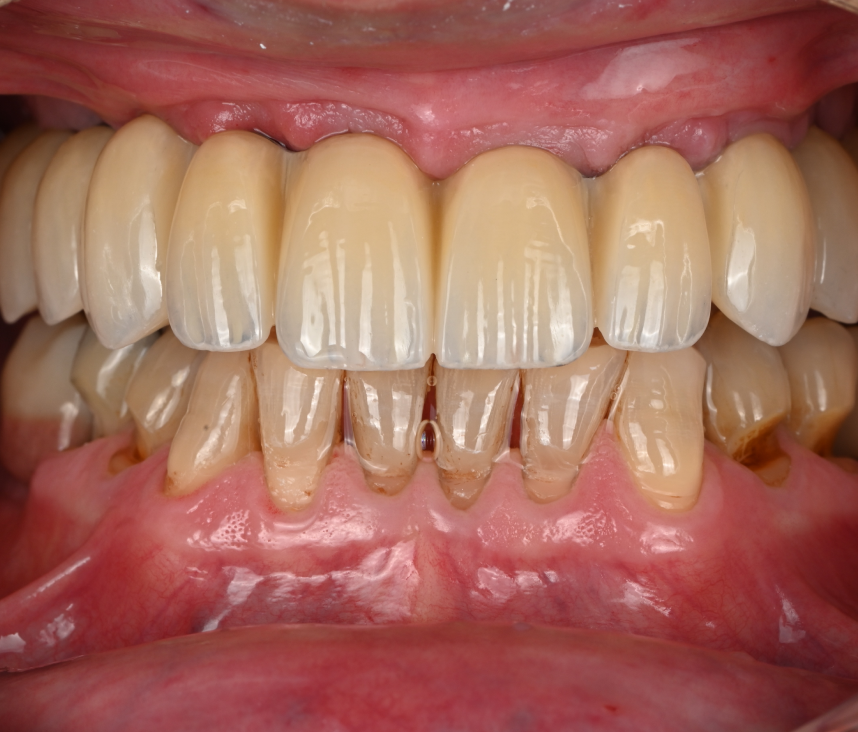

Cas cliniques

La réhabilitation globale est une solution complète pour ceux qui ont des problèmes de santé bucco-dentaire multiples et complexes. Elle consiste en un plan de traitement personnalisé, conçu pour traiter toutes les affections dentaires en une seule fois. Cette approche globale permet de restaurer l’harmonie du sourire, tout en améliorant la santé bucco-dentaire de façon durable.

Que vous souffriez de problèmes d’occlusion, de perte de dents, de maladie parodontale, ou d’autres problèmes dentaires, une réhabilitation globale pourrait être la solution pour vous. Au cabinet dentaire du Docteur Malthieu à Amiens, nous sommes fiers de pouvoir proposer cette approche intégrée à nos patients.